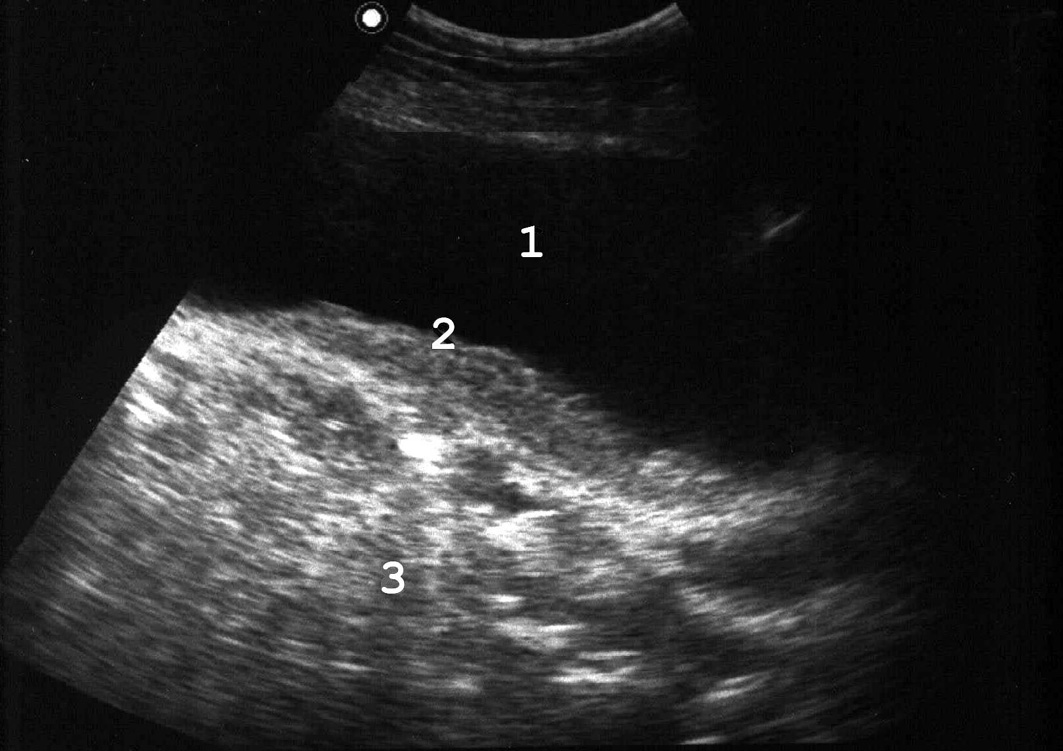

Рис. 4. Сонограмма мочевого пузыря в норме: 1 − мочевой пузырь; 2 − простата; 3 − стенка мочевого пузыря нормальной структуры и толщины. (Продольное сканирование, конвексный датчик 5 МГц, “Logiq-500”).

Рис. 5. При хронической задержке мочи вначале развивается гипертрофия мышечной оболочки мочевого пузыря: 1 − мочевой пузырь; 2 − увеличенная простата; 3 − утолщенная стенка мочевого пузыря. (Продольное сканирование, конвексный датчик 5 МГц, “Logiq-500”).